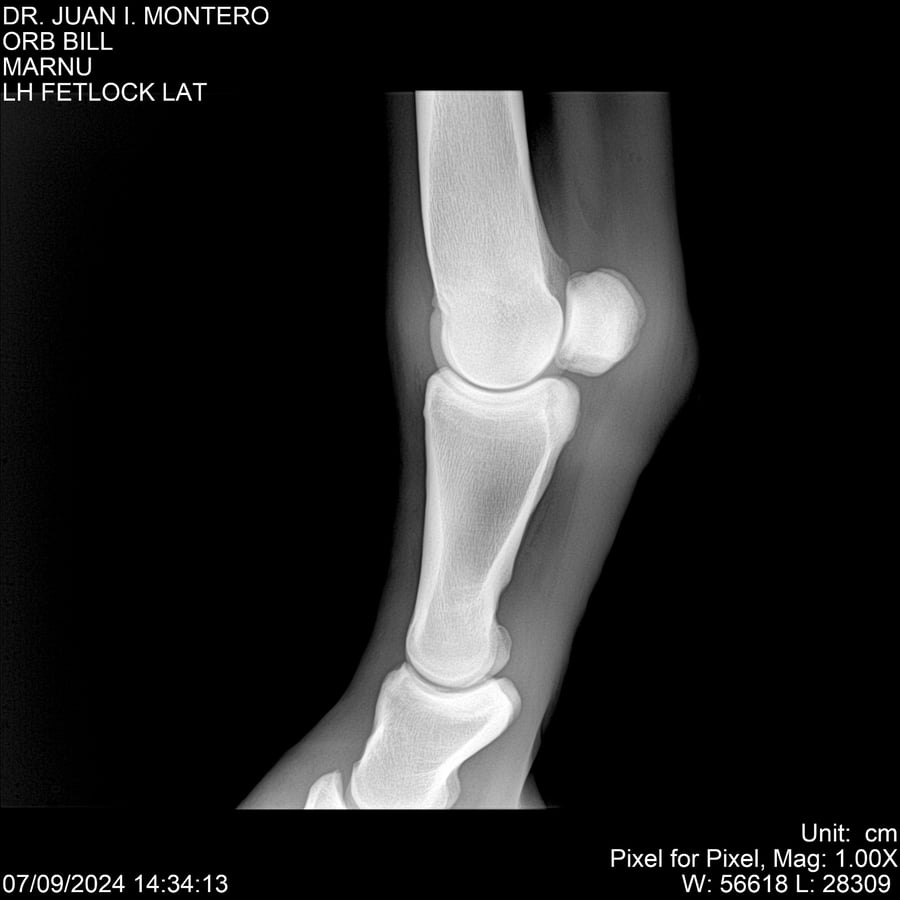

LOTE 7, ORB BILL 🔥 🔥 🔥 Lote Anterior Volver al remate Lote Siguiente Ficha Contacto Montevideo - Ficha del Lote Identificador: #282523 Categoría: Yeguarizos Montevideo - 83 Visualizaciones ClicData Contacto Empresa: Abelenda N. R., Walter Hugo Nombre*: Teléfono* : E-mail* : Mensaje Enviar Registrese gratis Este contenido Exclusivo está disponible sólo para usuarios registrados Ingresar